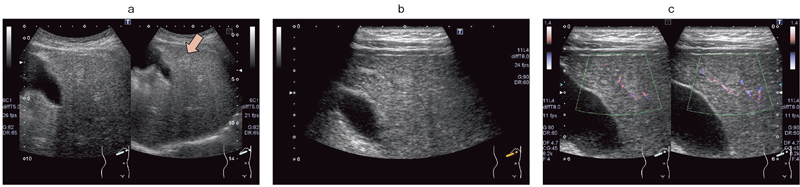

図2は,肝線維症の疑いで他院から紹介受診した30歳代の女性の症例である。肝実質が粗くて見えにくいと思われたが,実際には深部まで明瞭に描出されている。他院の画像診断ではわからなかった高エコー腫瘤が肝臓のS4に認められたため,高周波プローブに切り替え,微細な構造を確認したところ,辺縁低エコー帯と腫瘤内部の低エコー部が明瞭に描出された(図2 b)。また,高分解能,高フレームレート,低ブルーミングな血流イメージングを可能にする“Advanced Dynamic Flow(ADF)”で見ると(図2 c),流速1.4cmの低速表示でも腫瘤辺縁の門脈細枝や,その内側の肝静脈細枝までも描出され,非常に解像度が上がっていることがわかる。

図2 30歳代,女性,肝線維症疑いの症例 高エコー腫瘤がS4に認められ(a),高周波数プローブに切り替えたところ,辺縁低エコー帯および内部の低エコー部が明瞭に描出された(b)。 ADF では,低速の血流も血流シグナルとして描出された(c)。

図2 30歳代,女性,肝線維症疑いの症例 高エコー腫瘤がS4に認められ(a),高周波数プローブに切り替えたところ,

辺縁低エコー帯および内部の低エコー部が明瞭に描出された(b)。 ADF では,低速の血流も血流シグナルとして描出された(c)。